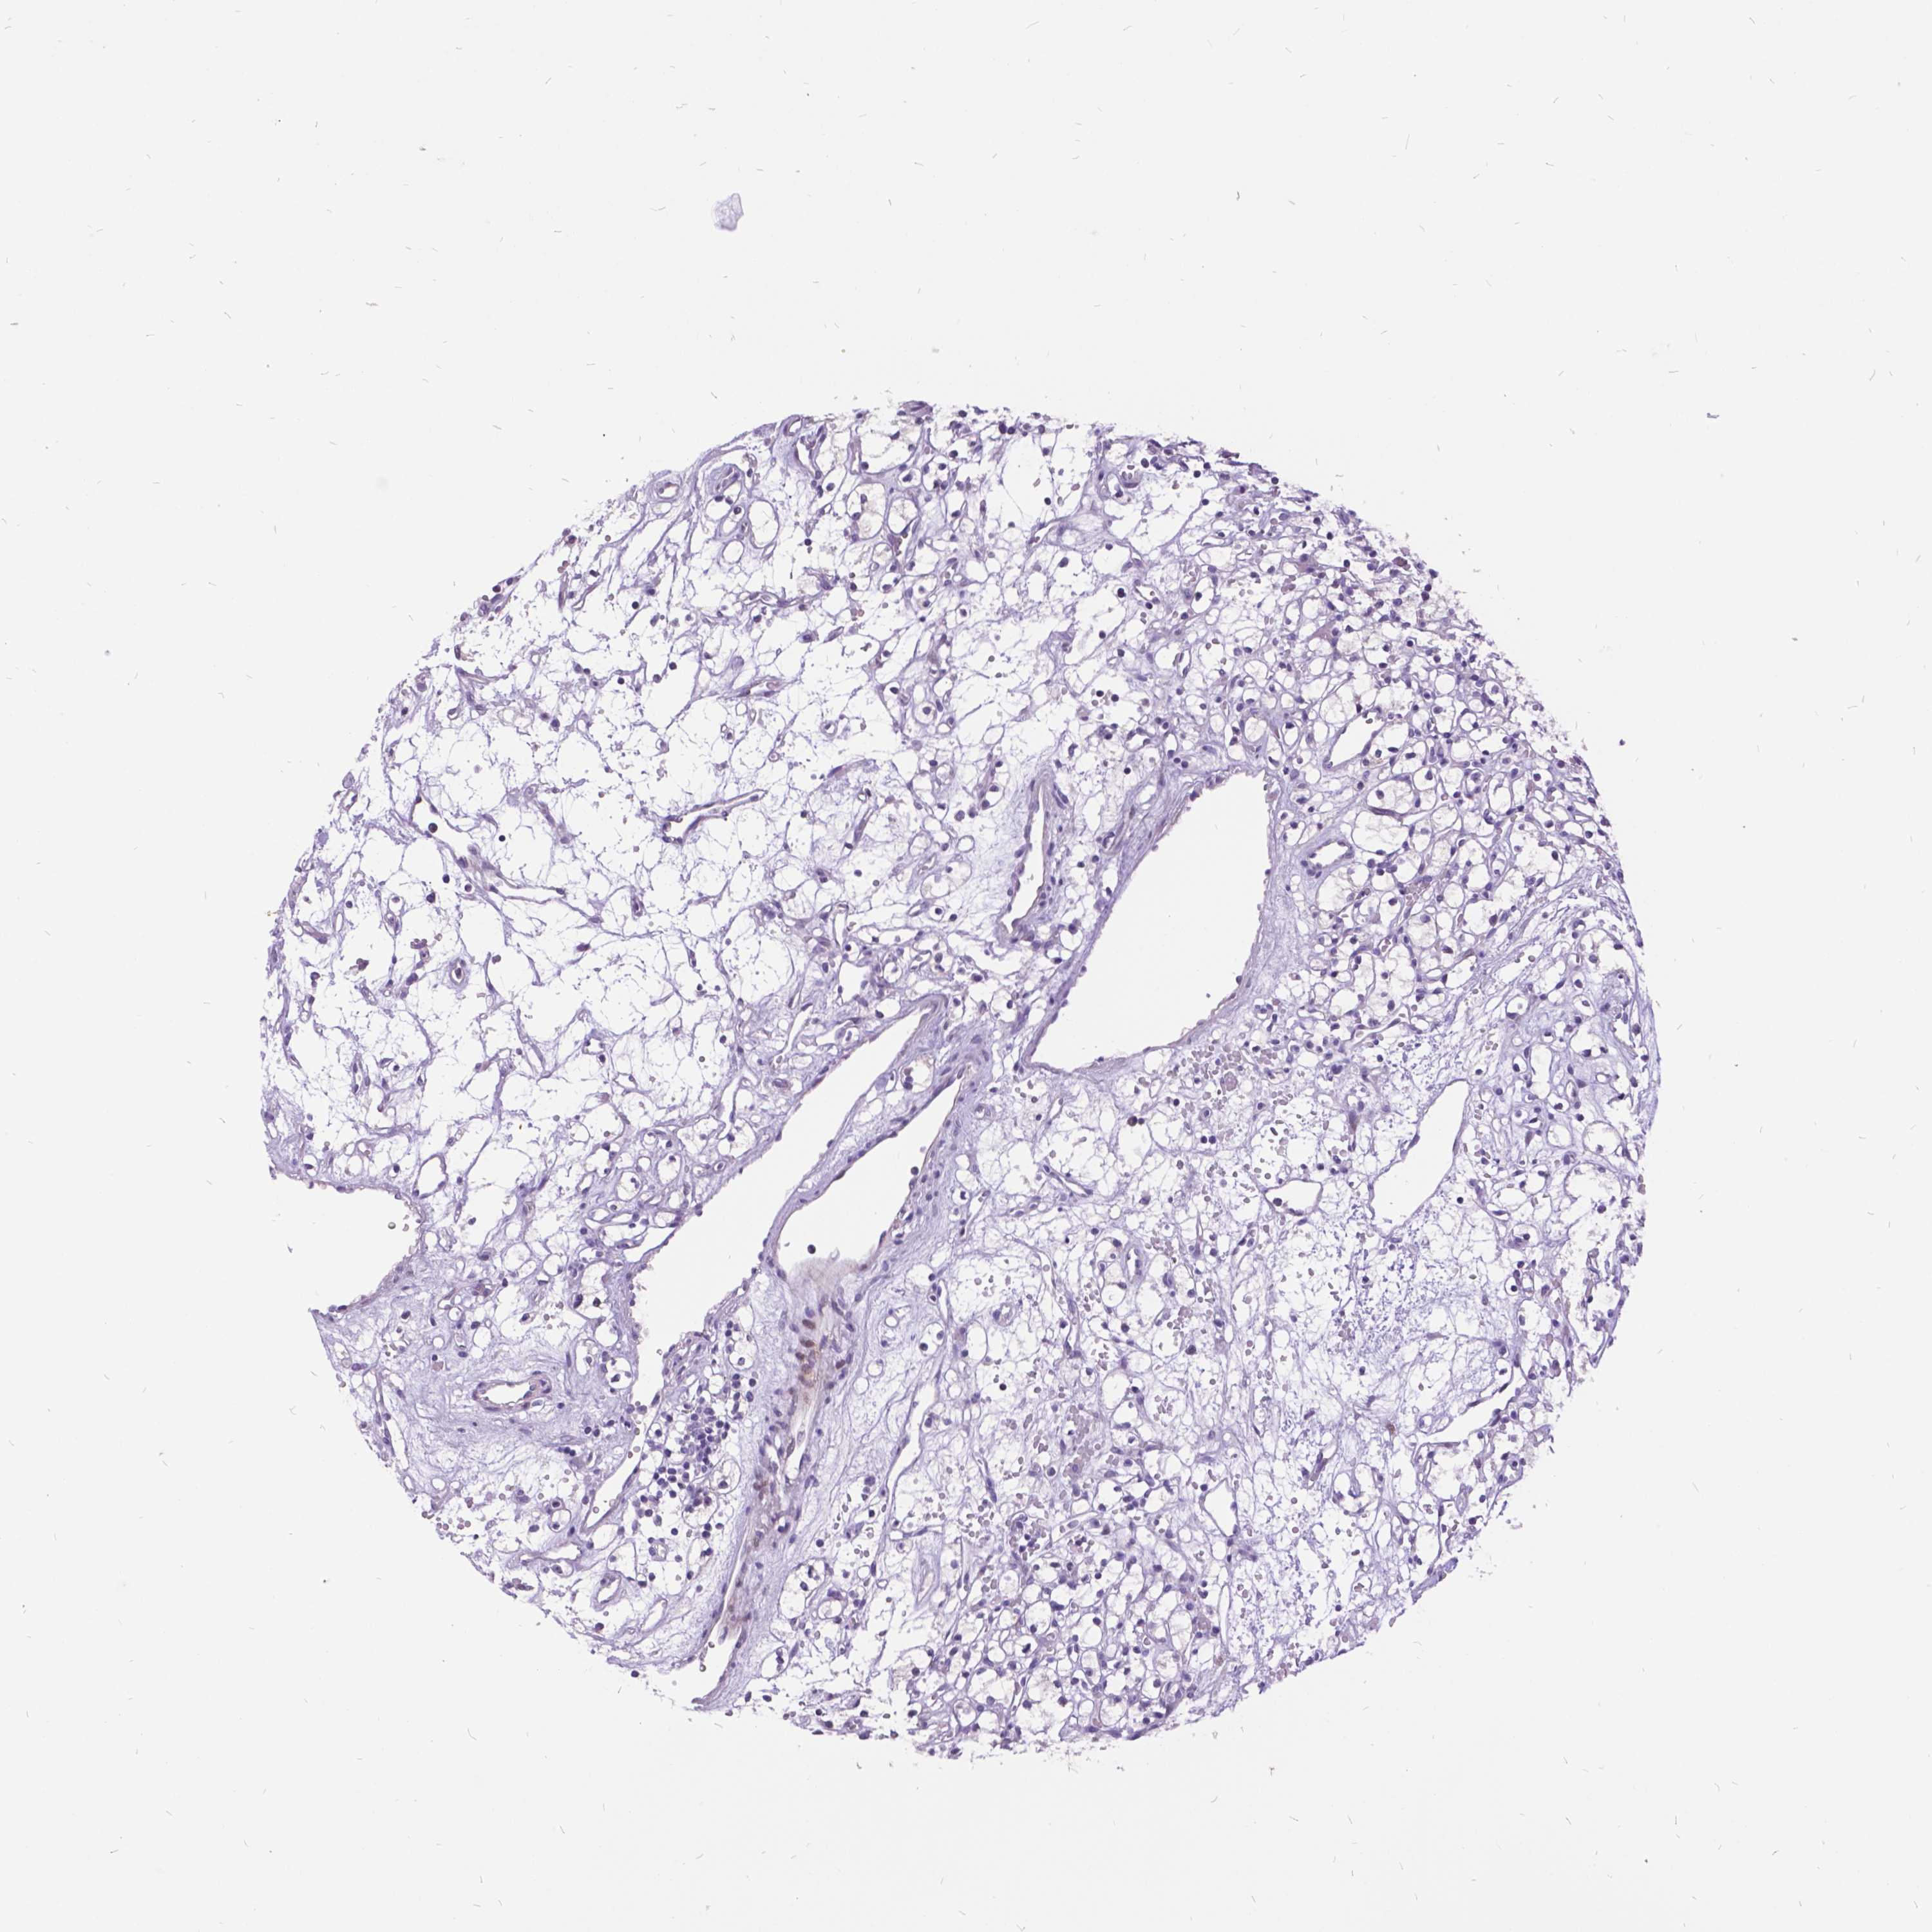

KIDNEY RENAL PAPILLARY CELL CARCINOMA (TCGA) - Interactive survival scatter ploti

The Survival Scatter plot shows the clinical status (i.e. dead or alive) for all individuals in the patient cohort, based on the same data that underlies the corresponding Kaplan-Meier plots. Patients that are alive at last time for follow-up are shown in blue and patients who have died during the study are shown in red.

The x-axis shows the expression levels (FPKM) of the investigated gene in the tumor tissue at the time of diagnosis. The y-axis shows the follow-up time after diagnosis (years). Both axes are complimented with kernel density curves demonstrating the data density over the axes. The top density plot shows the expression levels (FPKM) distribution among dead (red) and alive patients (blue). The right density plot shows the data density of the survived years of dead patients with high and low expression levels respectively, stratified using the cutoff indicated by the vertical dashed line through the Survival Scatter plot. This cutoff is automatically defined based on the FPKM cutoff that minimizes the p-score. The cutoff can be changed by dragging the vertical line or by entering a cutoff value in the square labeled "Current cut-off".

Under the Survival Scatter plot the p-score landscape (black curve; left axis) is shown together with dead median separation (red curve; right axis). Dead median separation is the difference in median mRNA expression between patients who have died with high and low expression, respectively. It is calculated as follows: median FPKM expression of dead patients with high expression - median FPKM expression of dead patients with low expression. This is intended to aid the user in visually exploring custom cutoffs and the associated p-scores and dead median separation.

Individual patient data is displayed and can be filtered by clicking on one or more of the category buttons on the top of the page. Categories describing expression level and patient information include: high, low, alive, dead, female, male and tumor stages. The scale of the x-axis can be toggled between linear and log-scale by clicking on the "x log" button. Mouse-over function shows TCGA ID, patient information and mRNA expression (FPKM) for each patient.

& Survival analysisi

Kaplan-Meier plots summarize results from analysis of correlation between mRNA expression level and patient survival. Patients were divided based on level of expression into one of the two groups "low" (under cut off) or "high" (over cut off). X-axis shows time for survival (years) and y-axis shows the probability of survival, where 1.0 corresponds to 100 percent.

ITGB6 is not prognostic in Kidney Renal Papillary Cell Carcinoma (TCGA)

Best expression cut offi

Based on the FPKM value of each gene, patients were classified into two groups and association between prognosis (survival) and gene expression (FPKM) was examined. The best expression cut-off refers the FPKM value that yields maximal difference with regard to survival between the two groups at the lowest log-rank P-value. Best expression cut-off was selected based on survival analysis .